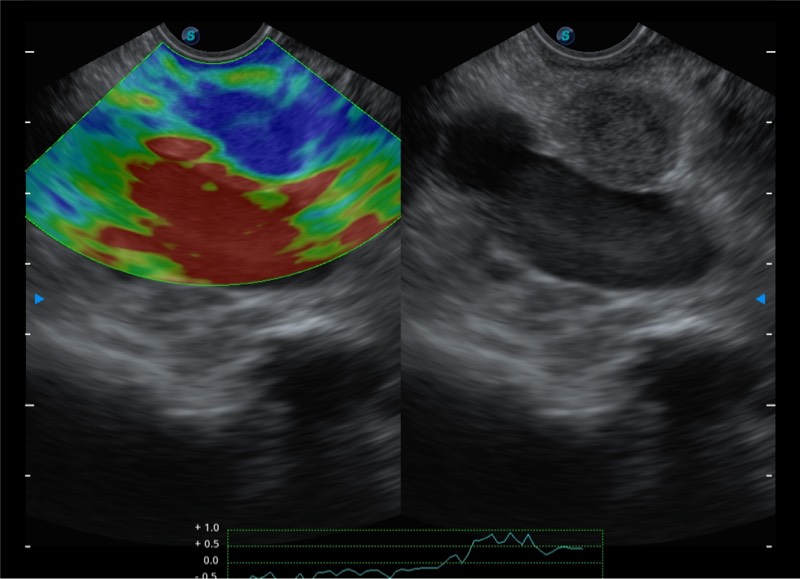

基于二十年的超声技术积累,乐玩lewin国际提供了最新一代的独立超声主机,在提供高质量图像的同时满足多学科使用。具备常见多普勒技术并提供弹性成像、声学造影等高端影像技术。新一代传感器具有更强的抗干扰能力并减少图像伪影。

• 4-12MHZ宽频输出